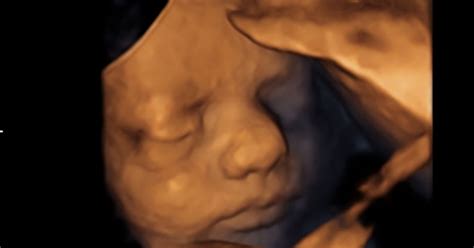

V 25. tednu nosečnosti so oči otroka že povsem razvite in otrok jih ves čas odpira in zapira. Na tej stopnji razvoja sicer še manjka barva šarenice, čeprav je bila določena že v trenutku spočetja na podlagi genetskega zapisa staršev.

V 25. tednu nosečnosti vaš otrok od temena do trtice meri približno 22 cm in tehta približno 700 g. Zaradi vedno boljše koordinacije lahko otrok zdaj stisne pest ali z rokami seže proti stopalom. Otrok se v trebuhu nenehno premika in mogoče že lahko prepoznate, kdaj njegove majcene roke ali stopala pritiskajo na trebušno steno - vidne so namreč lahko majhne modrice ali izbokline. Več kot jasno je tudi, da je otrok presenetljivo močan. Medtem se razvijajo tudi živci okoli otrokovih ust.